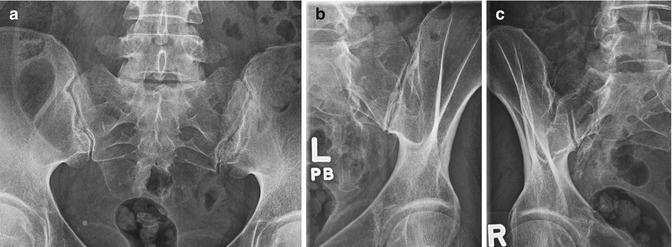

Phân loại trên X quang khớp cùng chậu:

| Độ | Mô tả | Đặc Điểm X-quang Chính | Ý Nghĩa |

| 0 | Bình thường | Khớp cùng chậu bình thường, bờ khớp rõ, khe khớp đều. | Không có VKCC trên X-quang. |

| 1 | Nghi ngờ | Thay đổi nhỏ, nghi ngờ, không rõ ràng, có thể bờ khớp không nét hoặc khe khớp hơi không đều nhẹ. | Nghi ngờ VKCC, cần theo dõi thêm và xem xét các yếu tố lâm sàng khác. |

| 2 | VKCC tối thiểu | Dấu hiệu VKCC nhẹ, ăn mòn và xơ hóa nhẹ bắt đầu xuất hiện, khe khớp có thể hẹp nhẹ. | VKCC mức độ nhẹ, có thể đủ tiêu chuẩn chẩn đoán VCSTD khớp nếu kết hợp với các tiêu chuẩn lâm sàng (theo Tiêu Chuẩn New York Cải Tiến). |

| 3 | VKCC rõ rệt | VKCC tiến triển, ăn mòn khớp, xơ hóa, hẹp khe khớp rõ ràng, đặc xương dưới sụn, ổ khuyết xương. | VKCC mức độ trung bình đến nặng, thường đủ tiêu chuẩn chẩn đoán VCSTD khớp theo Tiêu Chuẩn New York Cải Tiến. |

| 4 | VKCC dính khớp | Dính khớp hoàn toàn hoặc gần hoàn toàn, khe khớp biến mất, xương cùng và xương chậu dính liền. | VKCC giai đoạn muộn, dính khớp, thường là hậu quả của VCSTD khớp kéo dài và không được điều trị hoặc điều trị không hiệu quả. |

Minh hoạ: